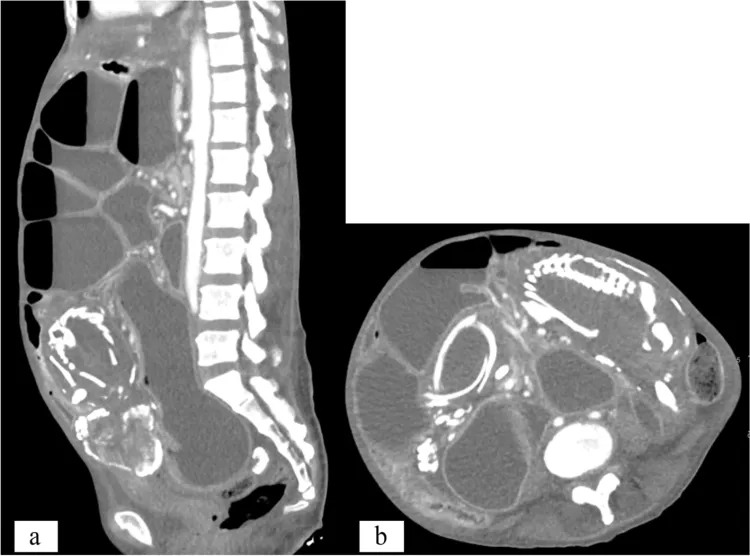

這個案例本周刊登於《BMC女性健康 BMC Womens Health 》,患者來自非洲剛果,長期為胃痙攣、消化不良所苦,進食後肚子總是咕嚕咕嚕作響,醫師在斷層掃描等檢查後發現,她體內藏了一個6*8英吋(約15.2公分*20.3公分)鈣化胚胎,應是源於她9年前的一次流產。

石胎(Lithopedion,或稱胎兒石化)多數是因子宮外孕,胎兒無法得到足夠血液供應死亡,身體卻無法排出死胎。有的胚胎若小,身體或可吸收,但本案的胚胎已經大到母體無法吸收,免疫系統誤以為外物入侵,體內機制便將胎兒鈣化包覆,保護母體不受感染。